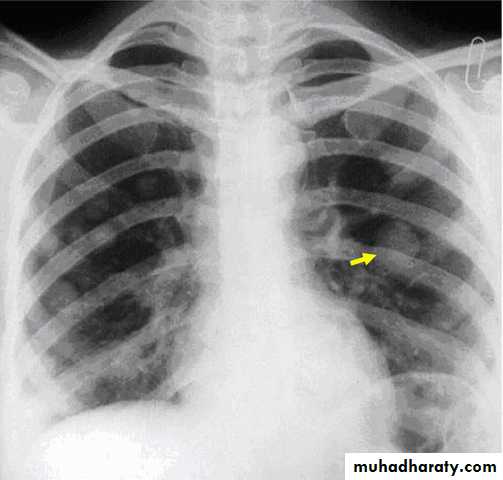

It is high but does not give useful distinction between mole and normal pregnancy. it is pivotal in diagnosis and follow up of GTD.Chest x- ray to exclude metastasis

Including pelvic examination at regular interval for first year until involuation of pelvic organ.Chest x ray

3. Chest x ray: If hCG titer plateau or rises.Chemotherapy is indicated if